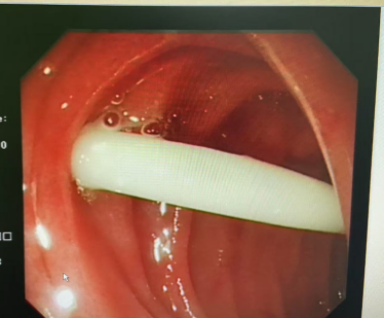

检查过程中,医生小心翼翼地查看患儿消化道内每一处角落,探查食道后未发现异物,便继续进镜。到达胃内时,医生在胃底发现了这枚金色别针异物,随即用异物钳稳稳夹持住异物尾端,缓慢退镜,最终顺利将别针取出,手术过程顺利。

术后,一直焦急万分的家属看到取出的别针时,瞬间流下眼泪。这泪水,既是此前担忧情绪的释放,也是对医护人员的感恩流露。